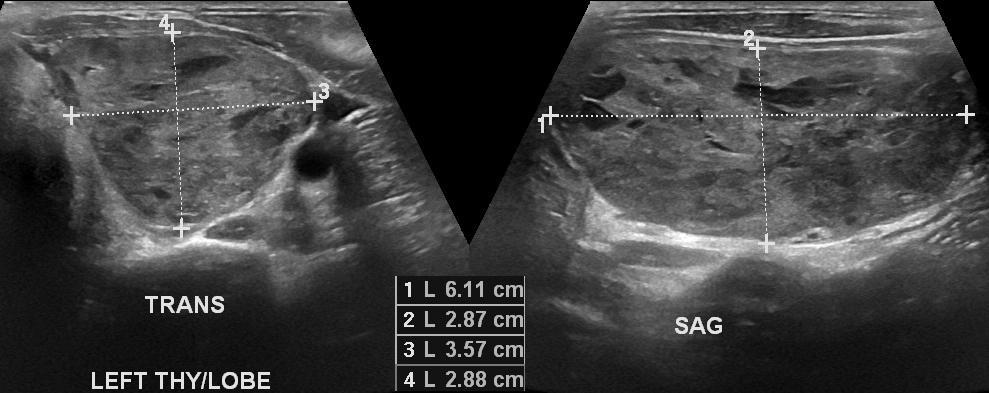

Ung thư tuyến giáp thể nhú (Papillary thyroid carcinoma)